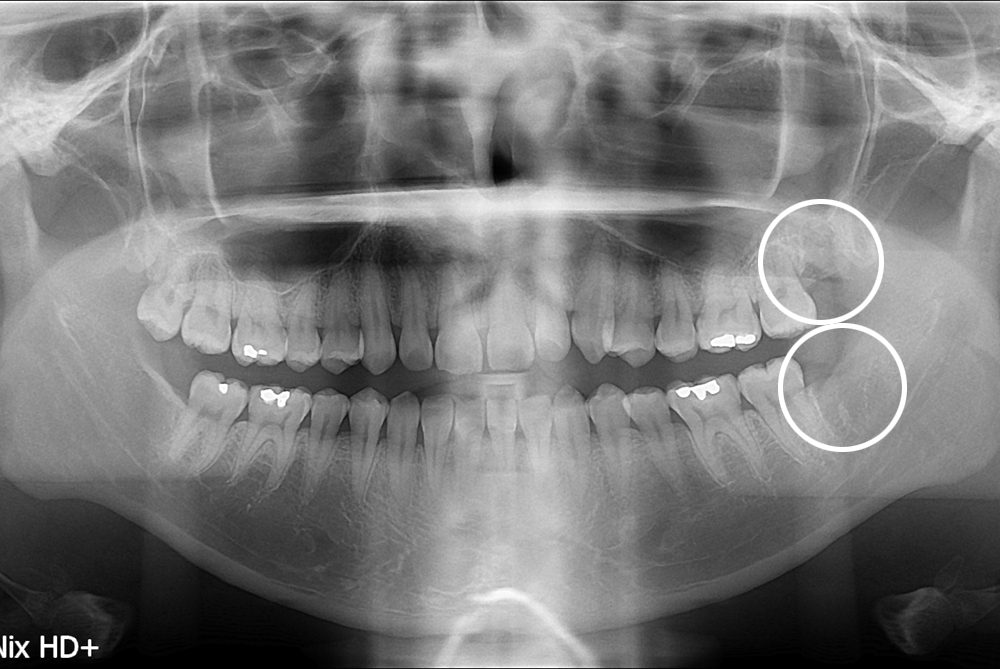

[사랑니] 난발치 사랑니 발치

치료전 : 2017-04-20